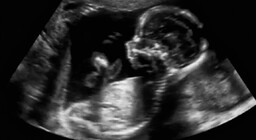

NatComms: эпигенетические изменения в плаценте связаны с расстройствами психики

Метилирование ДНК может быть связано с такими факторами, как диета, стресс и воздействие загрязняющих веществ.Газета.Ru

Результаты показали, что шизофрения, биполярное расстройство и большое депрессивное расстройство наиболее тесно связаны с изменениями в метилировании ДНК плаценты.Газета.Ru

Открытие того, что генетический риск может быть связан с метилированием ДНК плаценты, дает новые возможности для раннего выявления и профилактики психиатрических расстройств.Газета.Ru

Исследование также подчеркивает важность понимания того, как и когда генетические факторы влияют на развитие патологий.Газета.Ru